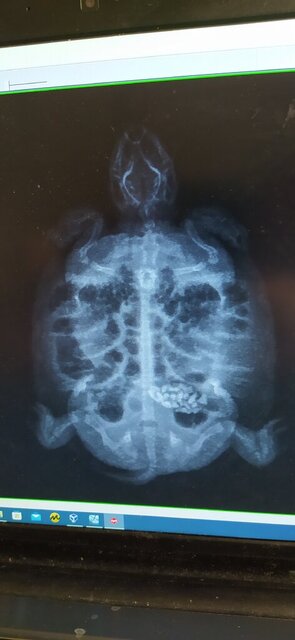

Сделали рентген сверху ,перевернули черепаху и тоже сделали ,какая кто есть кто не знаю ,в общем у меня 2 ренгена ,записали на диск с приложением ,это я с ПК открыл дома .

IMG_20231123_101453.jpg

IMG_20231123_102156.jpg

Мария осмотрела ,и сказала что малыш наелся камней или чего то плотного контрастного ....

@Softik да, это камни : ( видела в канале

но, конечно, у меня большие вопросы к ветеринарам, которые не могут повернуть черепаху лицом и боком к аппарату... это какая-то грустная шутка, потому что не первый раз такое встречаю, что они "не могут" другие проекции